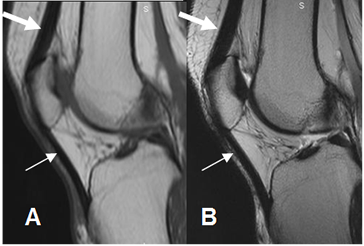

Fig 11. Mecanismo extensor normal.

A: RM sagital en T1 y B: RM sagital en T2. Tendón del cuadriceps (Flechas gruesas) y patelar (Flechas delgadas) de aspecto normal, hipointensos en ambas secuencias.

Fig 12. Mecanismo extensor normal.

RM sagital en T1. Zonas hipointensas en el tercio proximal del tercio proximal y distal del tendón patelar, por variante normal.